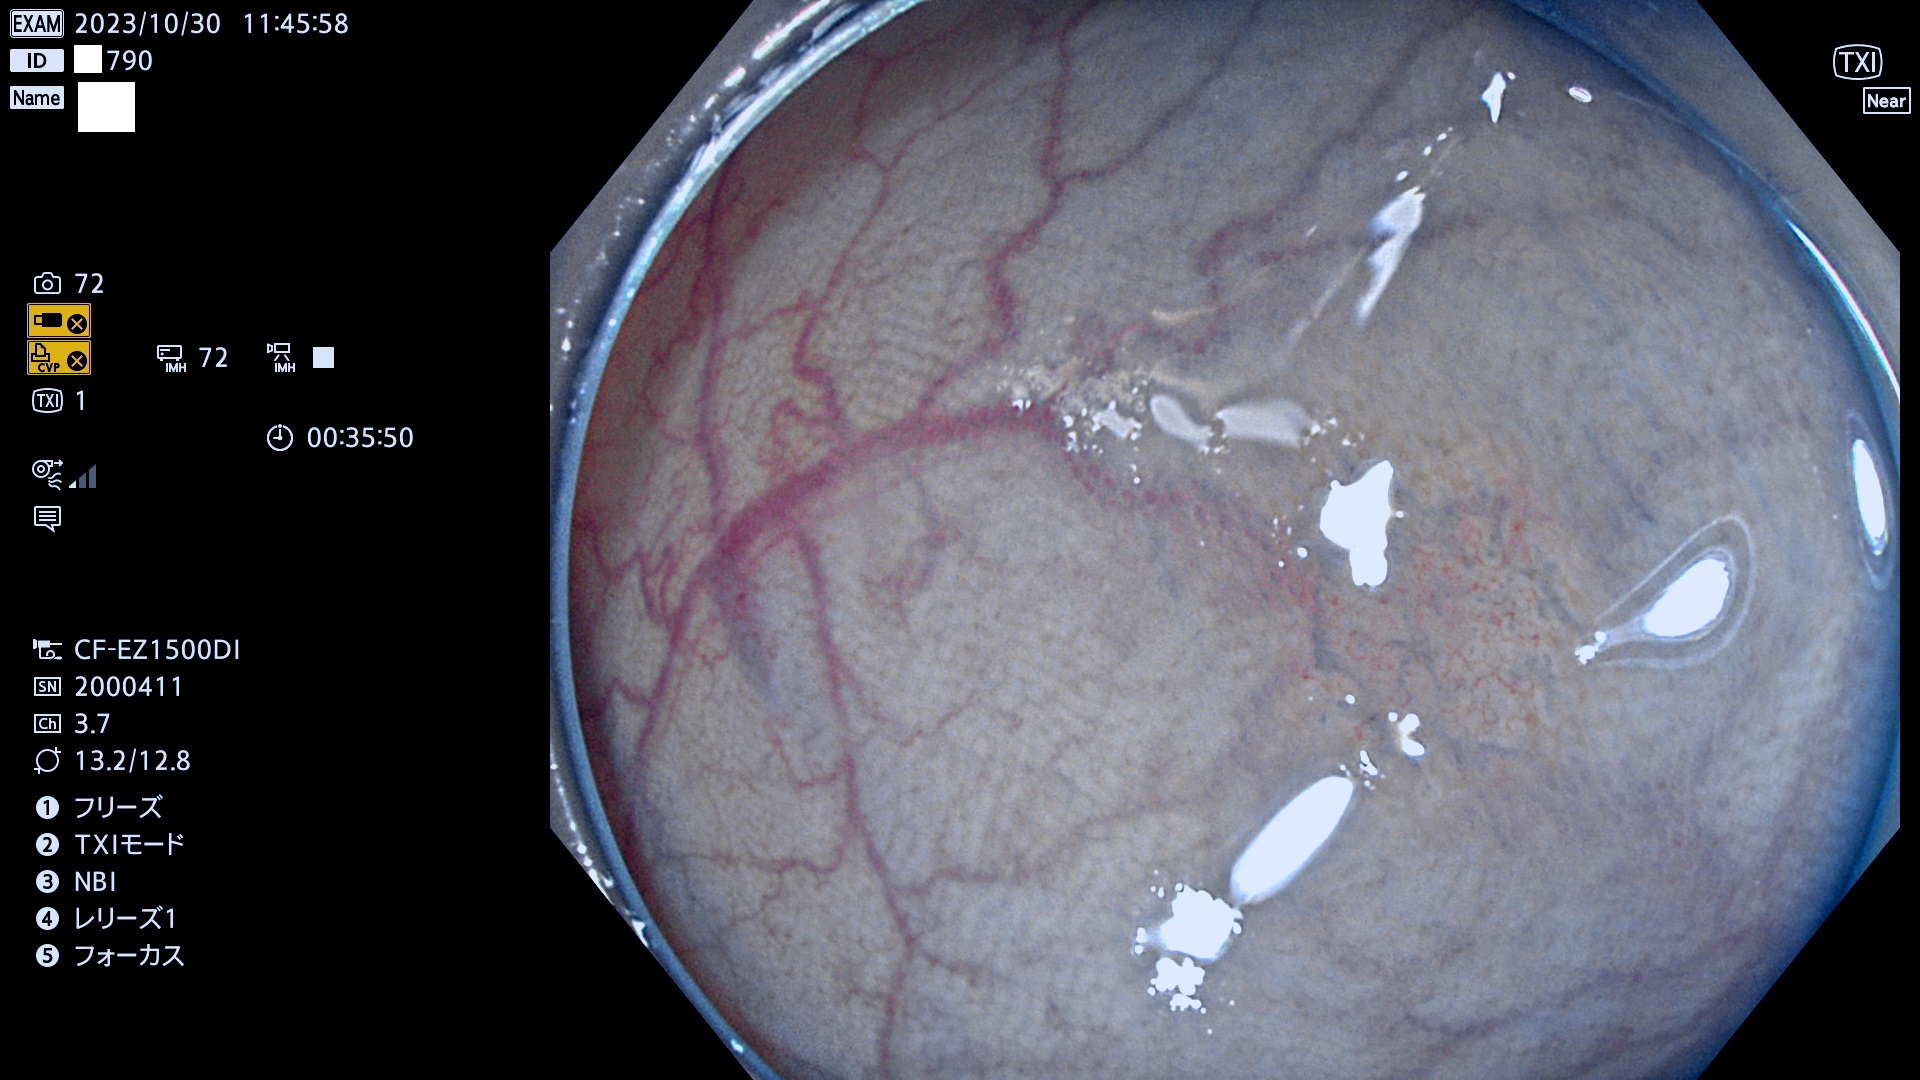

表面型腺腫(Flat Adenoma)の中で、完全に平坦な物をUb、陥凹している物をUcと呼びます。平坦隆起型(Ua)よりも、発見が難しく危険な病変です。このタイプは「内視鏡後・大腸癌の重要犯人」であり、この発見率は「腺腫発見率」よりも、重要な意味があります。

毎週の検査(木・金・土・日)に発見されたUb、Uc型・腺腫を、その週の日曜の夜にUPし1週間、提示します。

抽出の対象期間 2023年10月26日(木)〜10月30(月)の5日間(60件の検査)7件